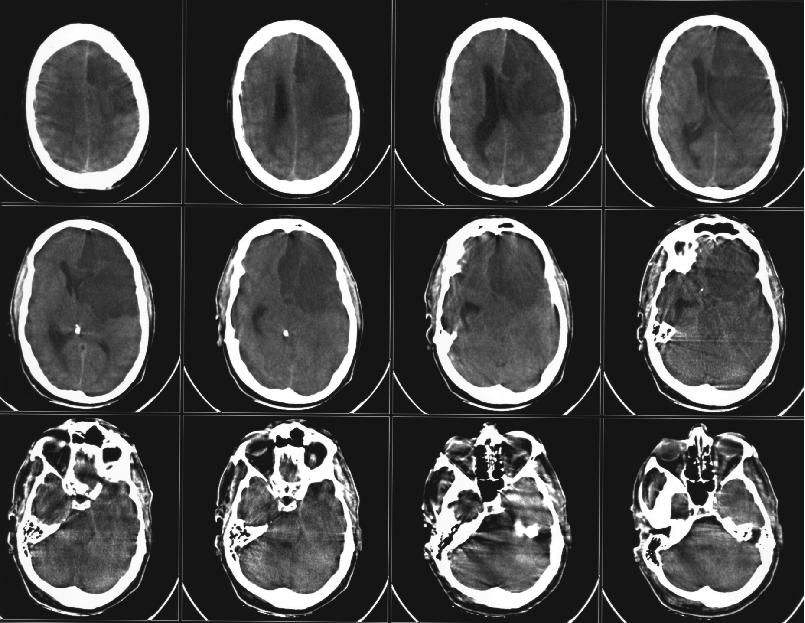

Schlaganfall, Hirnblutung oder Hirnverletzung